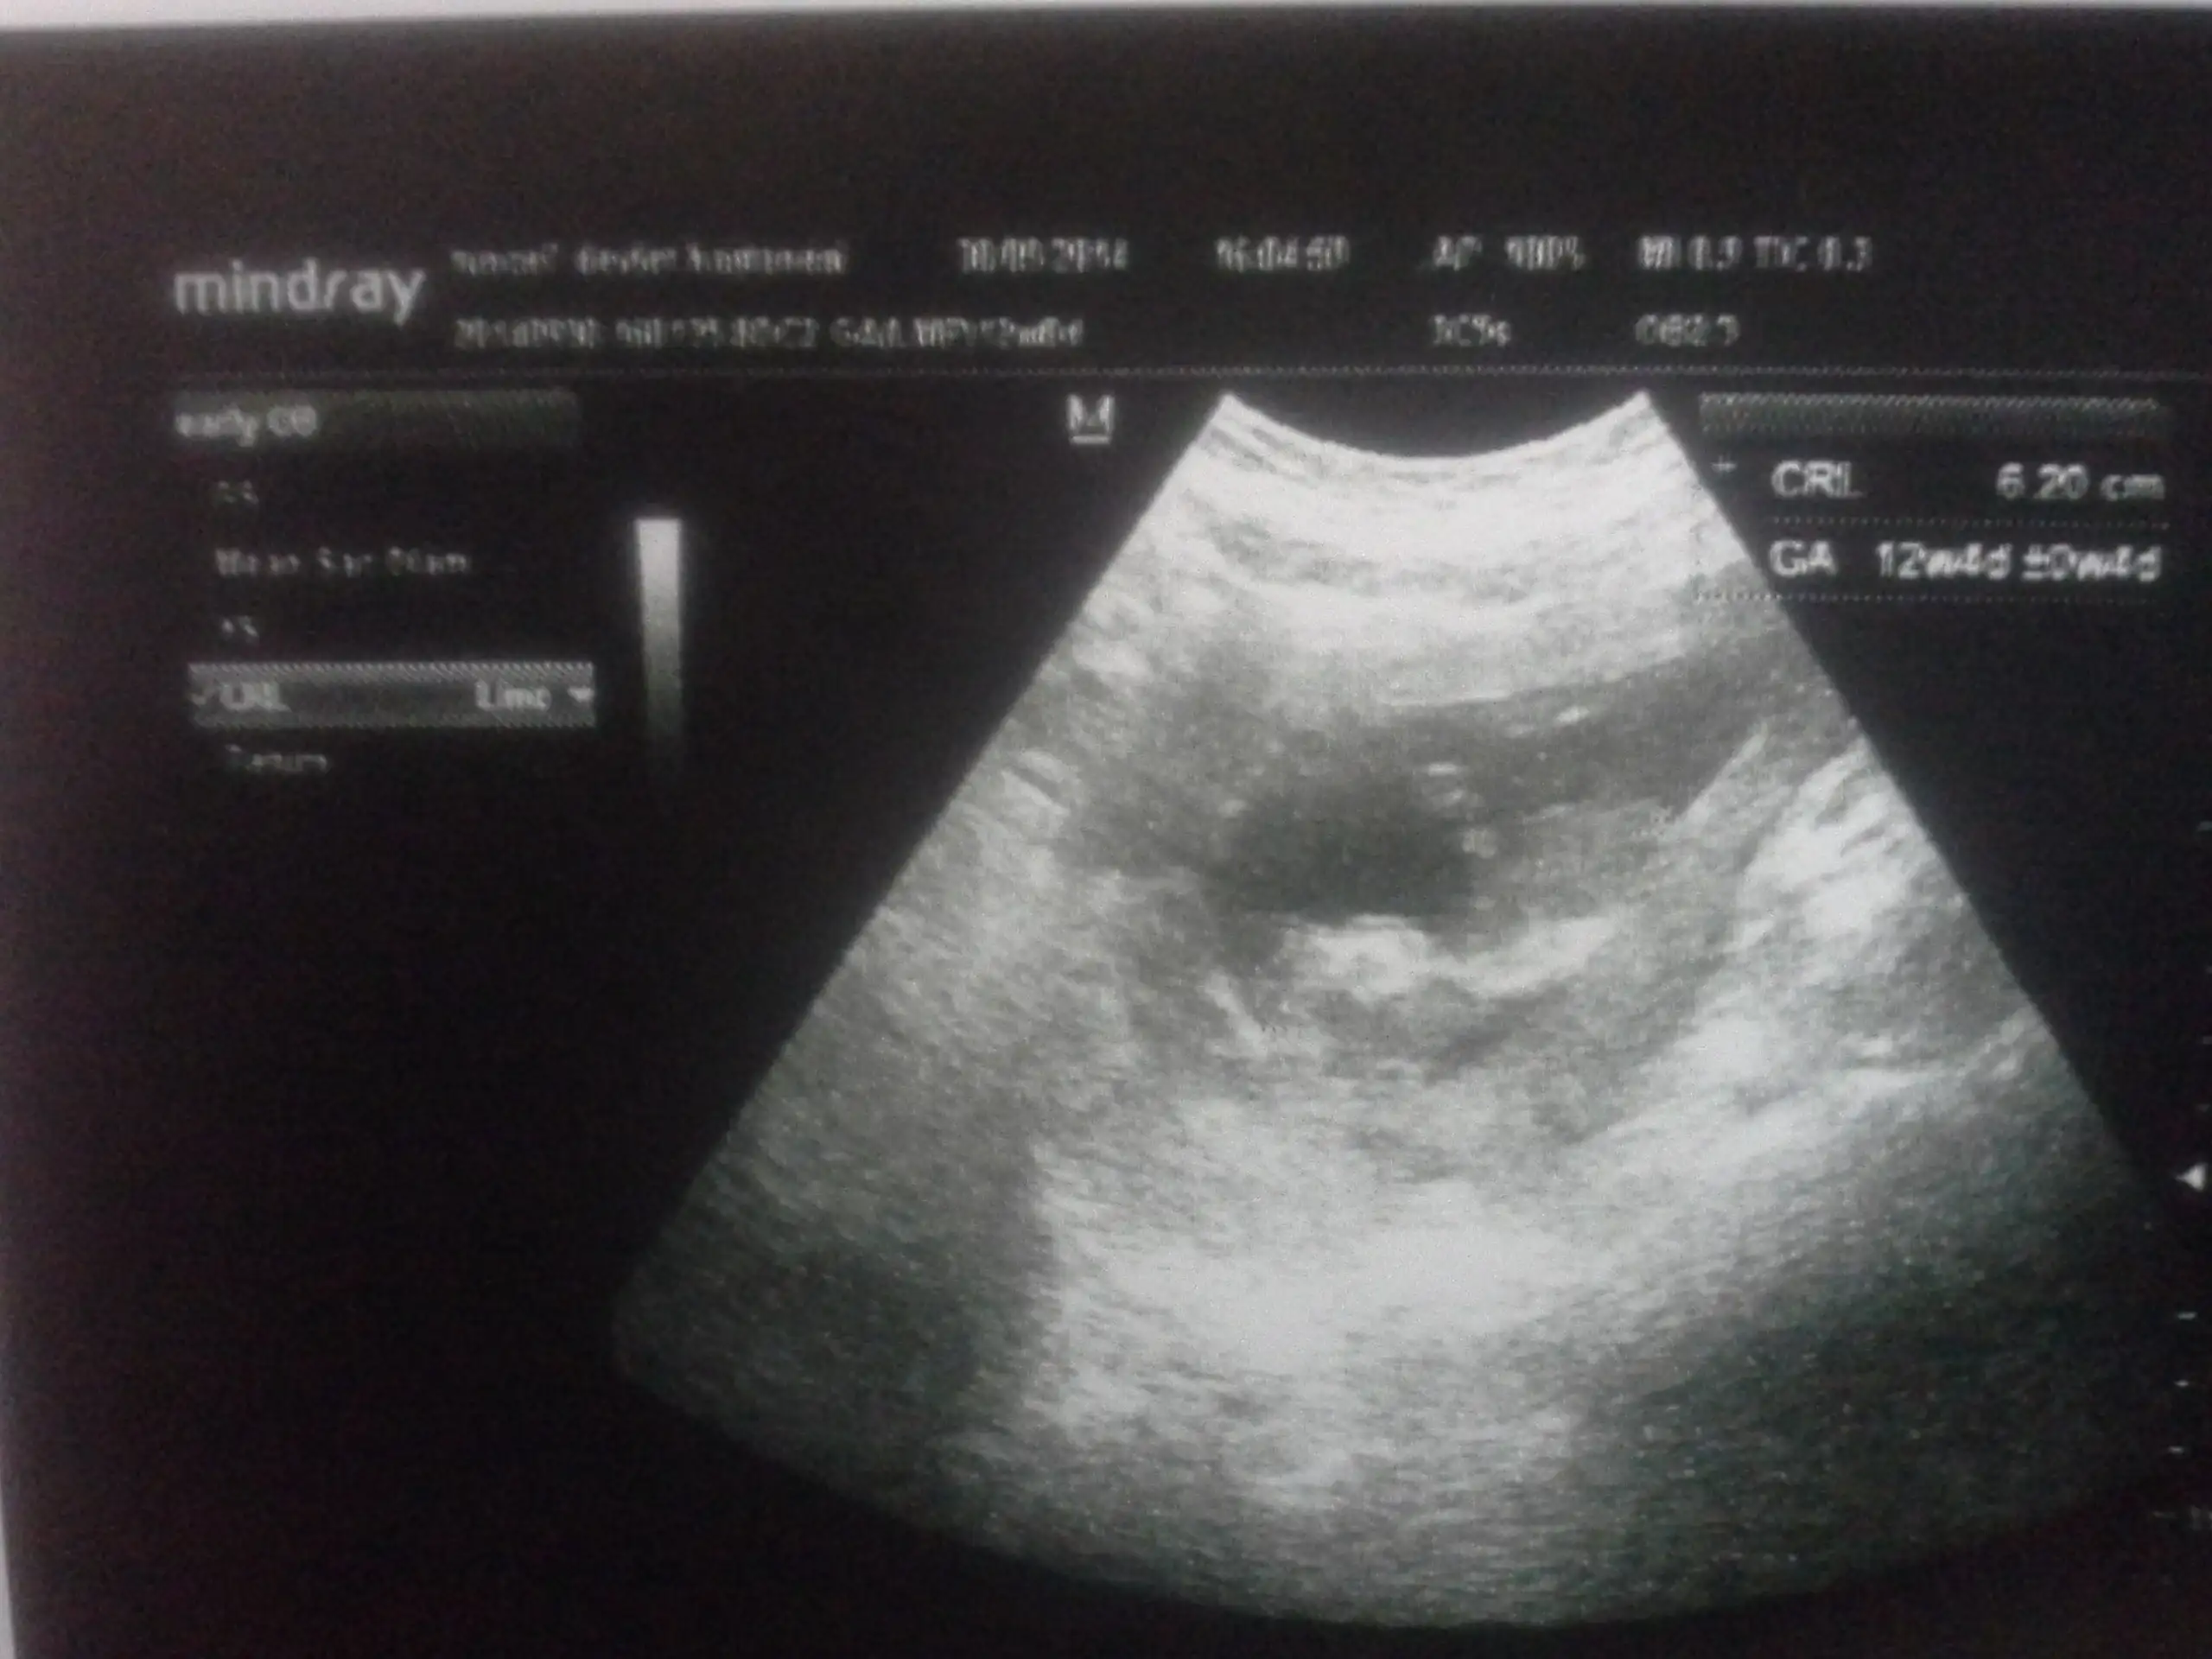

Kızlar bizde dün 12+0a girdik. Çok merak ediyorum cinsiyetimizi ama dr birşey soylemedi biran önce ogrensekte öyle hitap etsek yavrumuza :) sizce tahminen nedir :)

belli olmuştur heralde kız

Bana erkek dedi doktor. Asıl bayramdan sonra doktora gidince anlarız, bakıldığında küçüktü çünkü. O resmi gören kız diyor ama benim gibi. Yalnız Erkek gibi karnım zaten hiç yayvan değil.